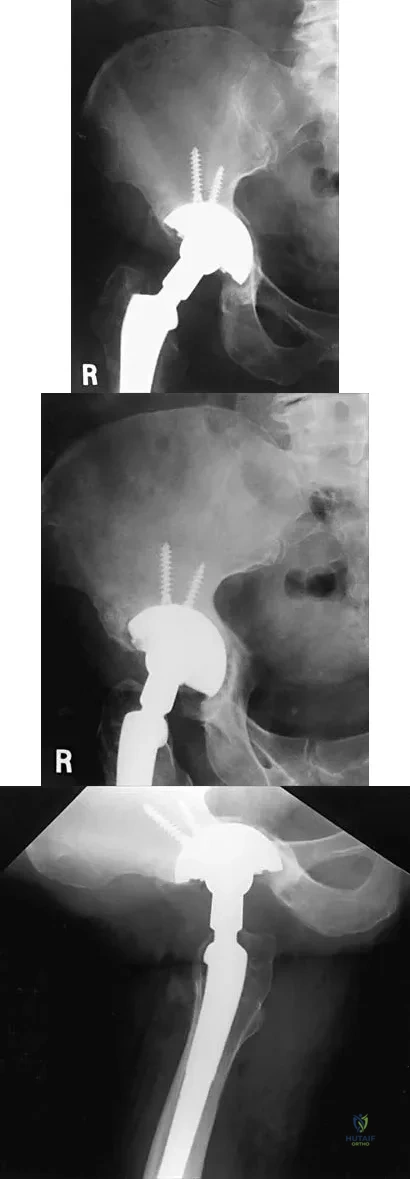

A 32-year-old man has posttraumatic arthritis after undergoing open reduction and internal fixation of a left acetabular fracture. A total hip arthroplasty is performed, and the radiograph is shown in Figure 18. What is the most common mode of failure leading to revision in this group of patients?

Explanation

Figure 44 shows the AP radiograph of the hip of a patient who underwent screw fixation of the acetabulum. Which of the following structures is at least risk for injury during screw placement in the acetabular component?

Explanation

Figures 21a through 21c show the radiographs of a 70-year-old woman who has persistent pain with activity after undergoing hip revision 6 months ago. Treatment should now consist of

Explanation